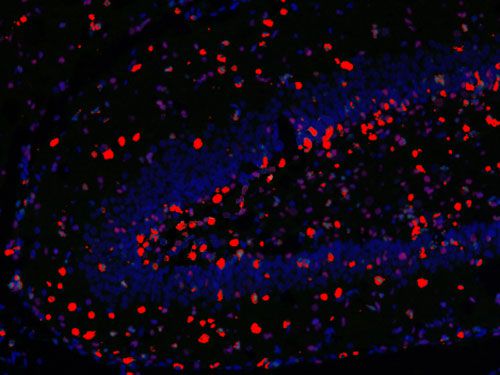

□免疫熒光多標陽性共定位分析:

測量整張掃描切片或者指定區域中單獨通道的數據以及指定共定位的數據(陽性面積或陽性率值表示,選其一)。

免疫熒光空間距離分析:

主要用來研究腫瘤微環境,炎性細胞和腫瘤細胞之間的距離關系等。

□分析一種指標標記的細胞周圍多少微米范圍之內另一指標標記的細胞數量,可以設置不同范圍;

□分析不同指標標記細胞之間的平均距離;

□以某處為界(如腫瘤灶、壞死灶或指定區域等)分析該區域多少微米范圍之內不同指標標記的細胞數量,例如腫瘤周圍500um內CD3陽性細胞的數量。